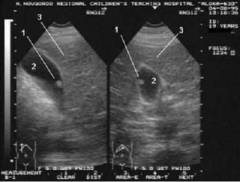

Диагностика включает ультразвуковое и эндоскопическое исследование. УЗИ использует звуковые волны высокой частоты, позволяя визуализировать желчный пузырь как темное овальное образование с тонкой стенкой. Полипы на УЗИ выглядят как светлые образования, растущие из стенки пузыря.

На УЗИ желчный пузырь выглядит как темное овальное образование с тонкой светлой стенкой. В норме стенка должна быть тонкой и ровной, а полость пузыря — однородного цвета. При наличии полипа на темном фоне видно светлое образование, растущее из стенки в полость. Форма светлого образования соответствует форме полипа: если он на ножке, выделяются ножка и шляпка. При нескольких полипах можно наблюдать несколько светлых образований. Цвет полипов может быть неоднородным: холестериновый или воспалительный полип будет белым, а аденоматозный полип на светлом фоне — с затемнениями.

Перед прикладыванием датчика место контакта обрабатывается гелем, что предотвращает попадание воздуха между датчиком и кожей. Для улучшения визуализации врач может попросить пациента лечь на правый бок. Полип желчного пузыря отличается от других образований тем, что не создает акустической дорожки, как камни в желчном пузыре, и не смещается при изменении положения тела.